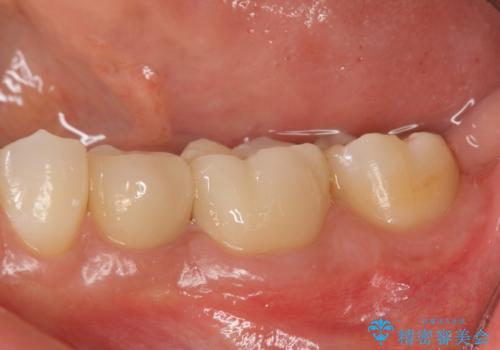

詰め物を除去したのち、虫歯を丁寧に除去することで神経を保存しながらセラミッククラウンによる補綴治療を行うことができました。

- 24.2万円(仮歯・ジルコニアクラウン×2)費用は治療当時の料金となります